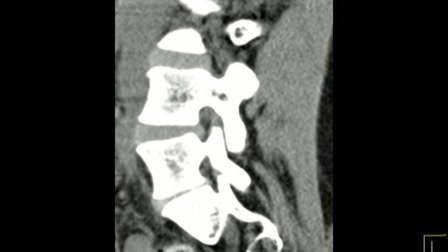

Autód vagy a gerinced?

Autód vagy a gerinced, neked mi a fontosabb?